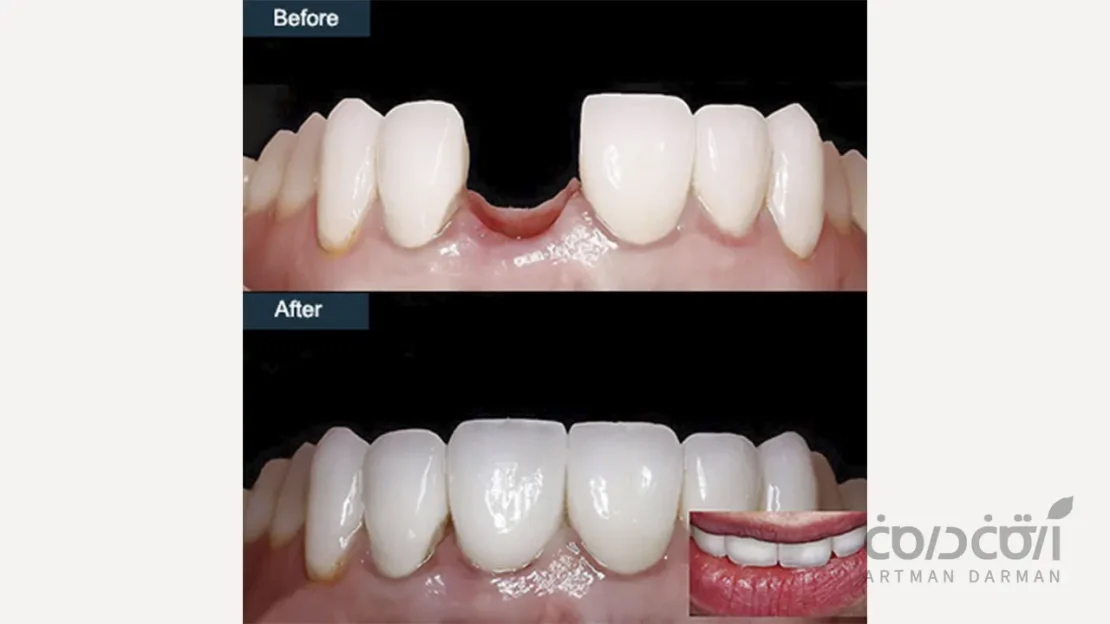

روکش دندان

بخش نهایی و قابل مشاهده درمان، همان روکش است که دقیقاً شبیه به یک دندان طبیعی ساخته می شود. جنس آن معمولاً از سرامیک های پیشرفته (مانند زیرکونیا یا E.max) است که هم استحکام لازم برای جویدن را دارند و هم زیبایی و شفافیتی مشابه مینای دندان طبیعی را ارائه می دهند.

این روکش به صورت کاملاً سفارشی برای هر بیمار ساخته می شود تا از نظر رنگ و فرم، با دندان های مجاور خود غیرقابل تشخیص باشد.